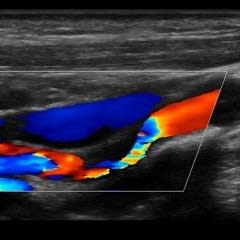

Vascular Services

Allow our dedicated team to put you at ease, while we boast about having top of the range equipment and overqualified staff. Outstanding patient care comes as standard here at NumiScan North London.